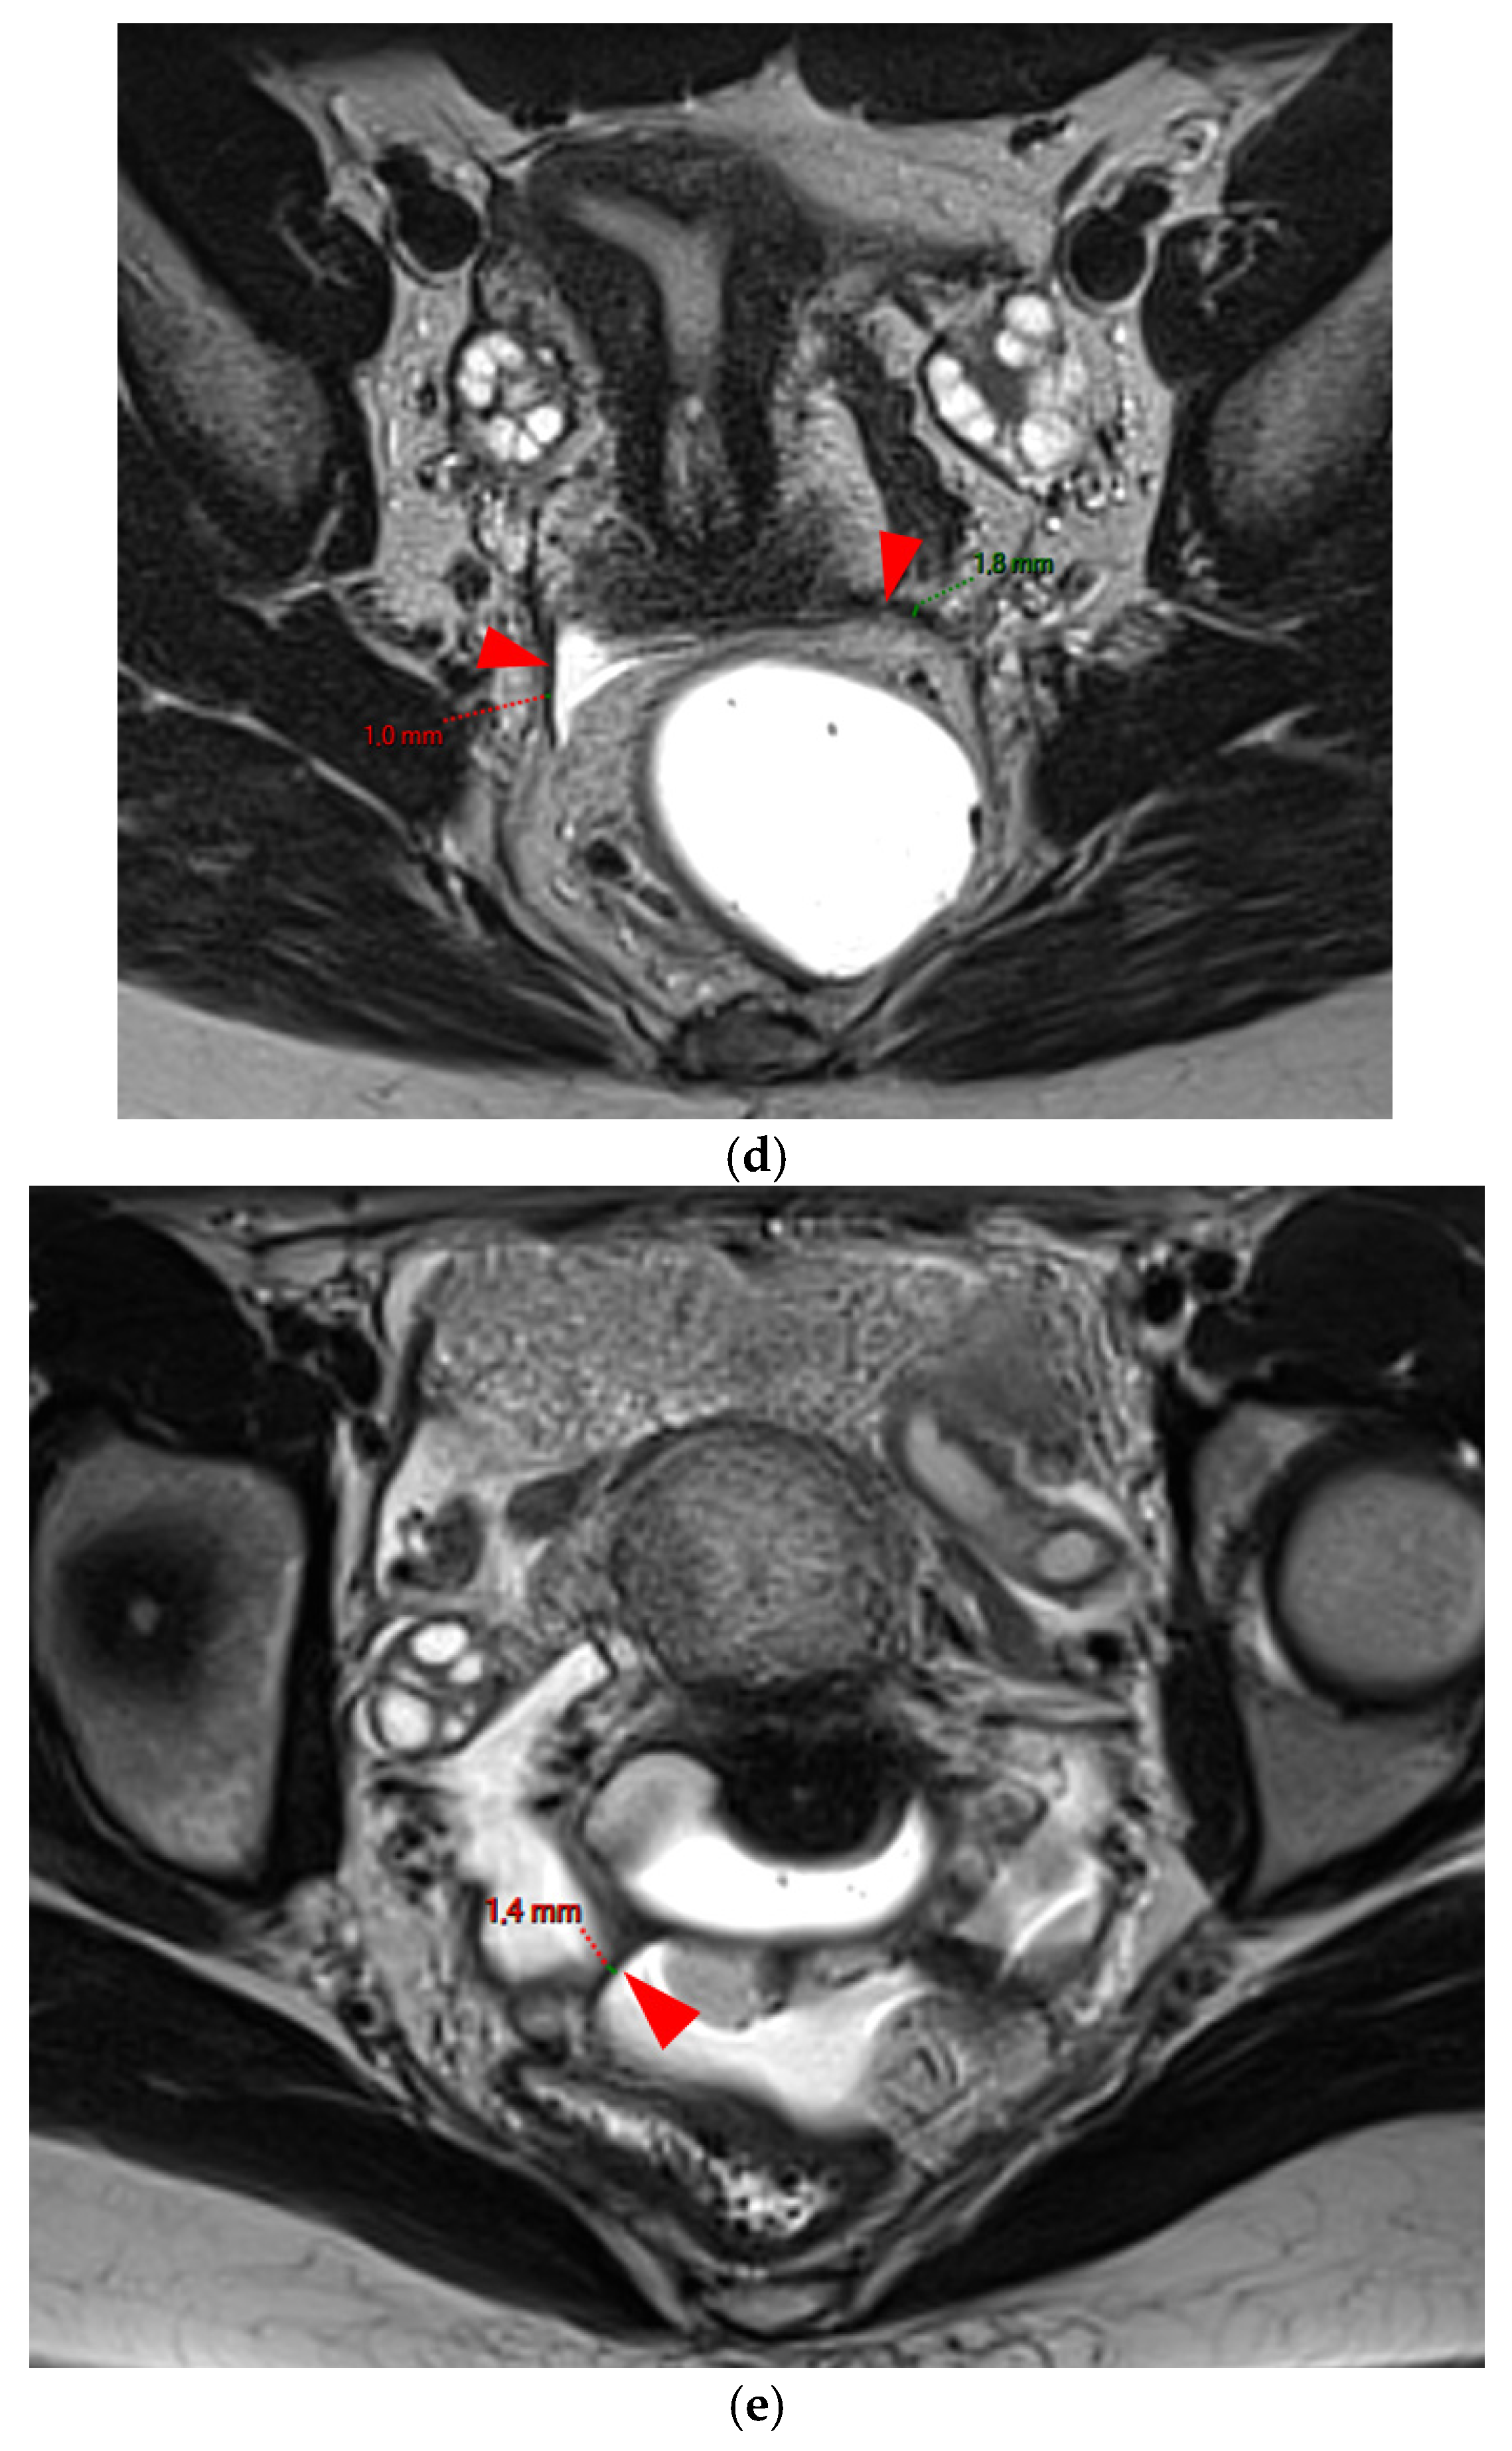

Figure 2. Pelvic MRI scans of five patients with visible but thin (≤2 mm), smooth, and regular USLs (HTD type 2). (a) Sagittal T2WI: right USL (arrowhead). (b) Sagittal T2WI: right USL (arrowhead). (c) Axial T2WI: right USL (arrowhead). (d) Axial T2WI: left and right USLs (arrowheads). (e) Axial T2WI: right USL (arrowhead).

A type 2 USL (Figure 2) is visible on MRI scans as a curvilinear T2 hypointense structure that mainly originates from the posterior uterine wall at the uterocervical junction, where the torus uterinus is located, and courses dorsocranially toward the sacrum. A type 2 USL is either visible but not measurable due to its minimal thickness (i.e., ≤1 mm), or visible and measurable but thin (i.e., between 1 mm and 2 mm, inclusive of 2 mm). It appears smooth with regular margins and often displays a longitudinally tapering shape.

Figure 3. Pelvic MRI scans of three patients with thick (>2 mm), smooth, and regular USLs (HTD type 3A). (a) Sagittal T2WI: a thick (2.8 mm), smooth, tapering-shaped left USL (arrowhead). (b) Axial T2WI: regularly thickened (3 mm) right USL with a smooth surface (arrowhead). (c) Axial T2WI: regularly thickened (4.1 mm) right USL with a smooth surface (arrowheads).

A type 3 USL appears as thickened (i.e., >2 mm), and can be classified either as type 3A (PPV = 75%; FPR = 25%) or as type 3B (PPV = 80%; FPR = 20%).

A type 3A USL (Figure 3) maintains a smooth appearance with regular margins and often retains a tapering shape despite its thickening.